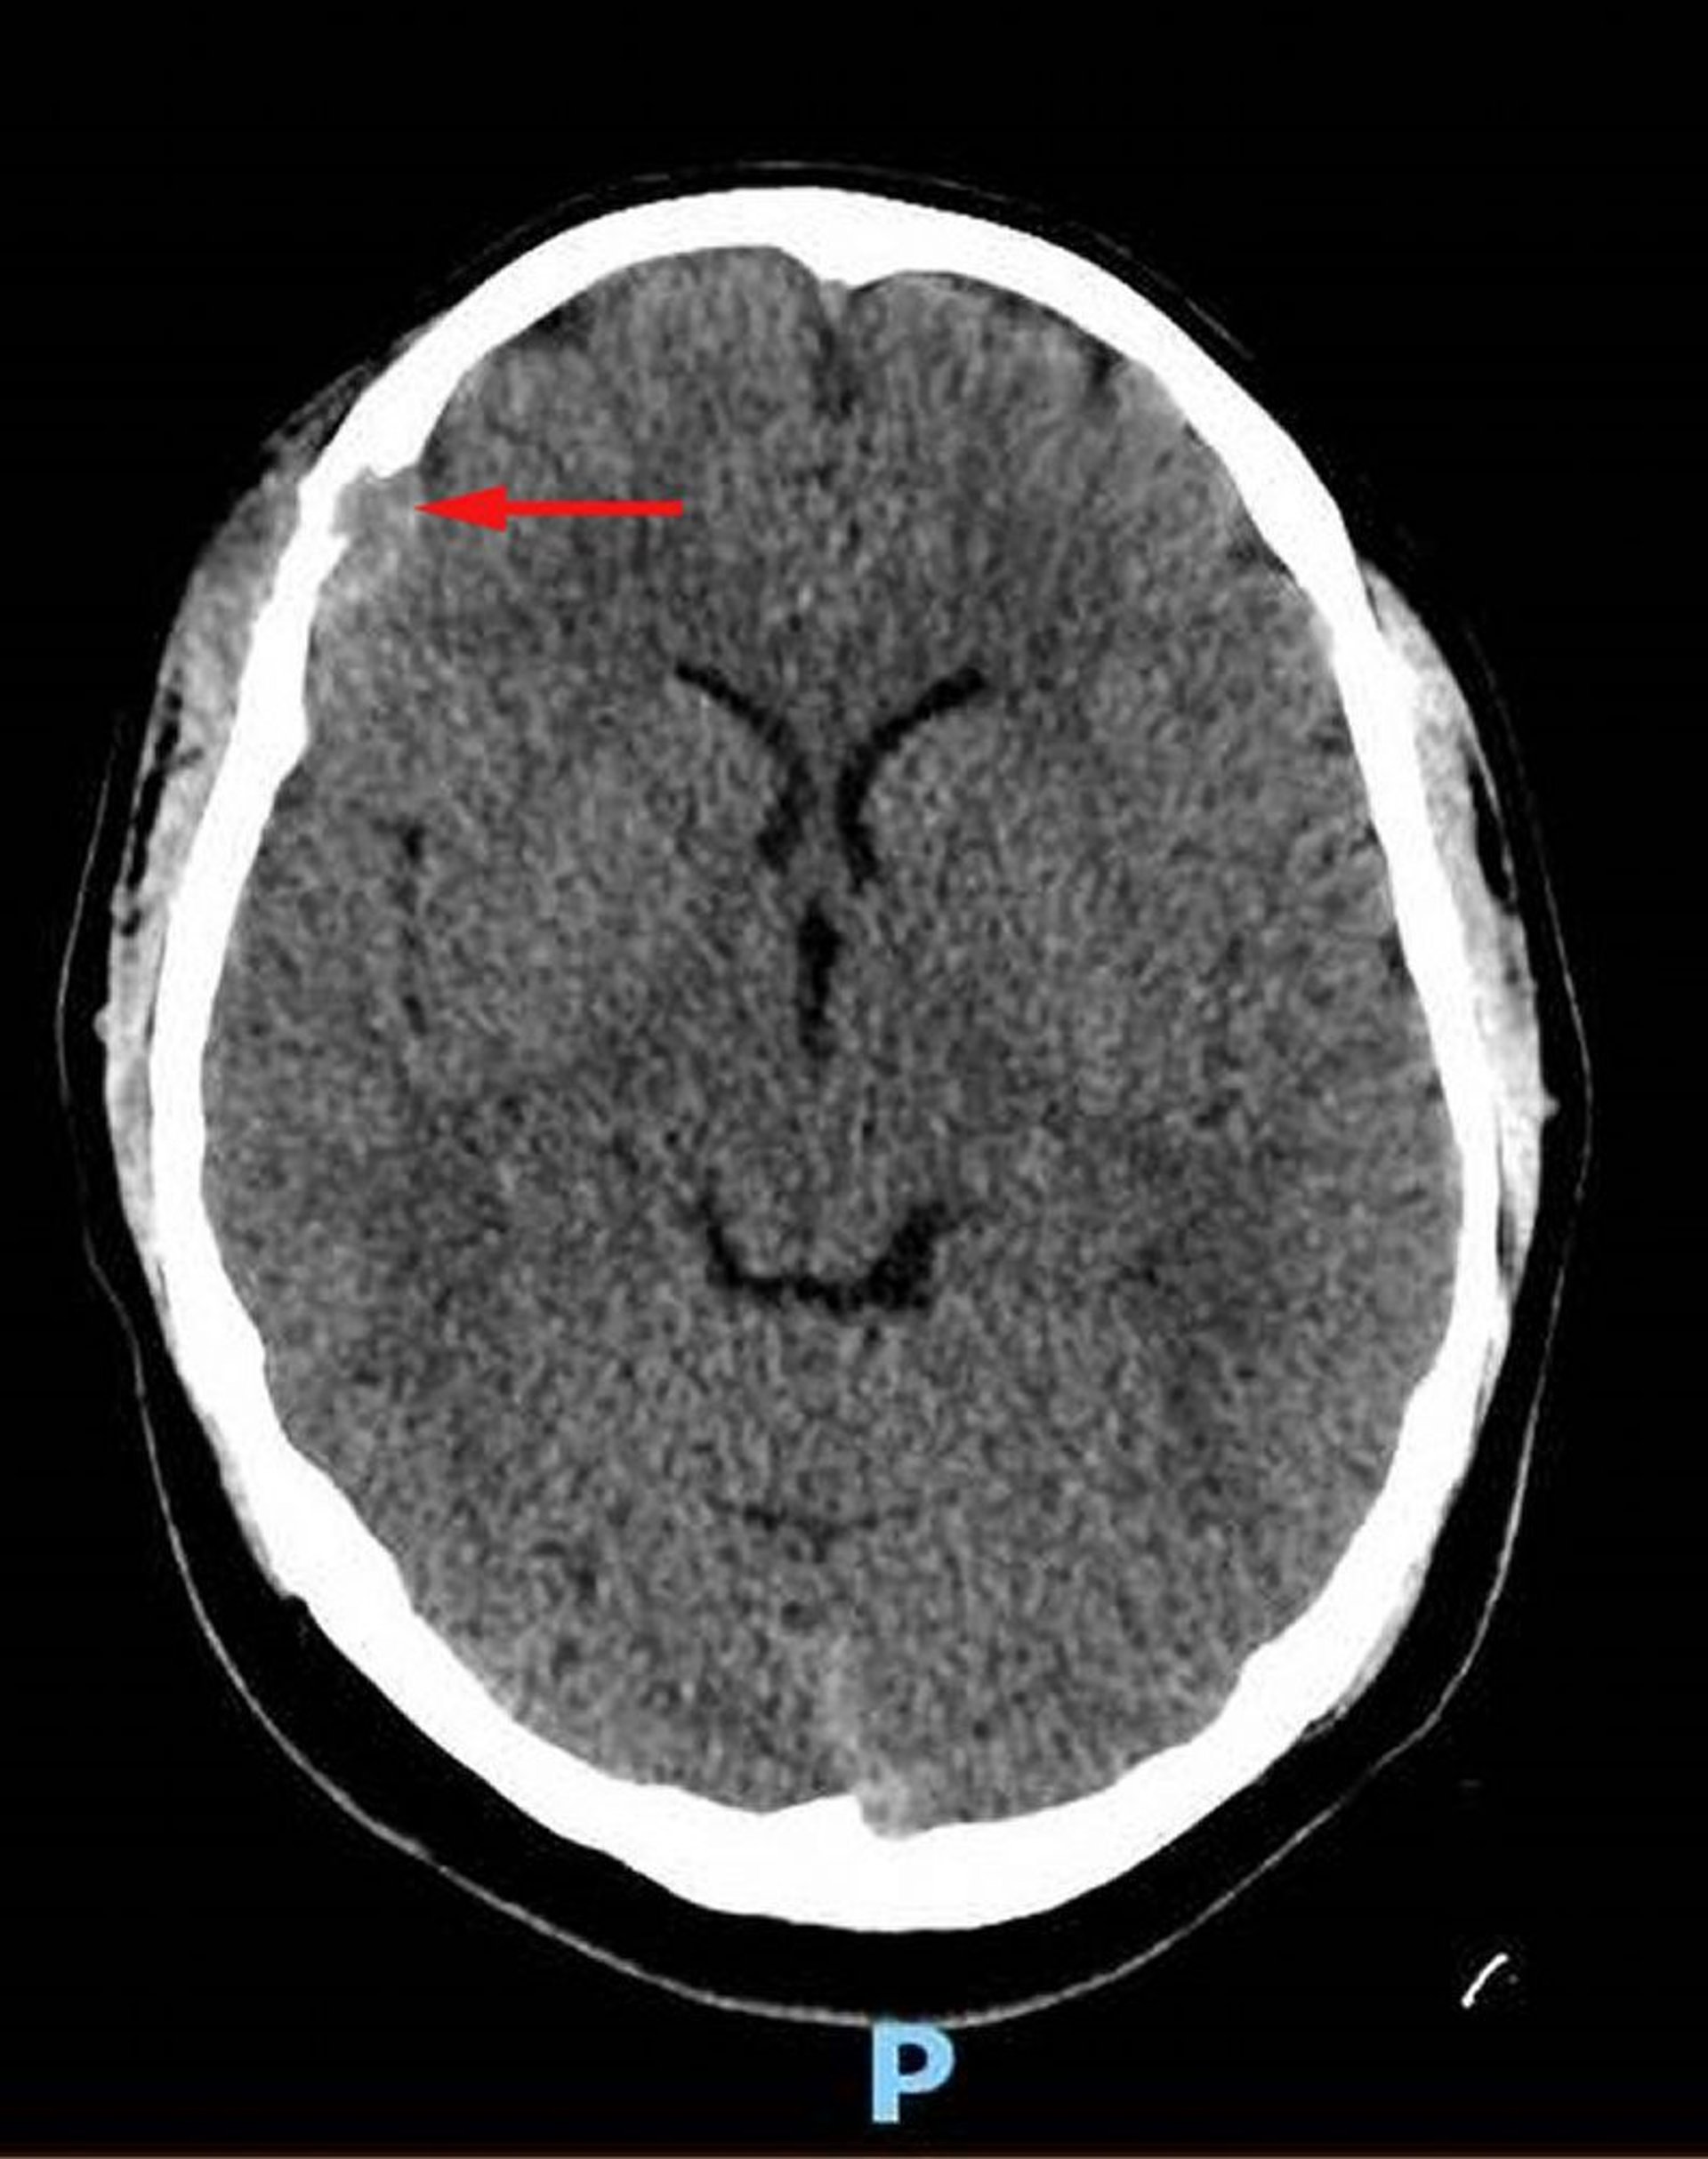

Istiocitosi a cellule di Langerhans (TC dell'encefalo)

Questa immagine mostra una lesione dei tessuti molli nell'osso frontale destro con associata distruzione ossea ed estensione intracranica dei tessuti molli nello spazio durale (freccia rossa). È presente un tessuto molle asimmetrico sovrastante il cuoio capelluto. La biopsia era diagnostica per l'istiocitosi a cellule di Langerhans.

Image courtesy of Carolyn Fein Levy, MD, and Jeffrey M. Lipton, MD, PhD.